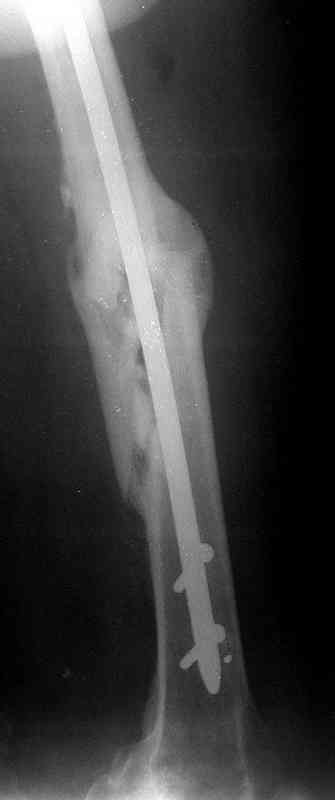

по его наружной поверхности послеоперационный рубец - рана зажила первичным натяжением. При измерении длины бедер обнаружено укорочение левого бедра на 4,5 см. На рентгенограммах этого бедра: ось конечности правильная, отмечается захождение основных костных фрагментов по длине, проксимальный конец штифта выступает слишком медиально и высоко относительно большого вертела, периостальная мозоль незначительна.22.12 - через 6 месяцев после операции, произведенной в ЦРБ, нами по поводу замедленно консолидирующего перелома левой бедренной кости с ее абсолютным укорочением под наркозом произведена операция: удаление штифта, закрытый блокирующий интрамедуллярный остеосинтез перелома левого бедра штифтом без рассверливания (UFN) длиной 40 см, диаметром 10 мм с блокированием только проксимальных отверстий (динамический остеосинтез). Наложен аппарат Илизарова на 4 полукольцах с целью удлинения укороченного бедра. Послеоперационное течение без особенностей. Ежедневно осуществляли дистракцию отломков на 1 мм. Через 3 недели после операции больной выпи-сан на амбулаторное лечение с продолжением дистракции отломков. В течение 1,5

месяцев дистракции укорочение левого бедра удалось полностью устранить. 22.02.00, т.е. через 2 месяца после повторного остеосинтеза, больному произведено дистальное блокирование штифта двумя винтами и демонтирован аппарат Илизарова. В течение 2 недель после операции больной ходил с помощью костылей, потом 2 недели с тростью. Опороспособность и функция оперированной конечности полностью восстановились через 4 недели после операции.